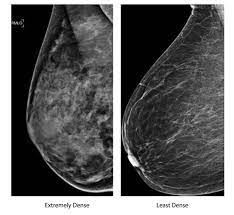

When to see a doctor. Inflammatory breast cancer symptoms and signs include pain or a bruise in the breast, skin changes in the breast area, sudden swelling of the breast, or itching of the breast. What does breast cancer look like on mammograms? Mammograms will often detect areas that are more dense than normal breast tissue or that have little flecks of calcium within milk ducts. Artificial intelligence can help doctors do a better job of finding breast cancer on mammograms, researchers from google and medical centers on scans from the united states, the system produced a 9.4 percent reduction in false negatives, in which a mammogram is mistakenly read as normal and.

A F Inflammatory Breast Cancer 35 Years Old Female Patient With Download Scientific Diagram from www.researchgate.net If breast cancer is picked up by further tests (either in the. See your doctor promptly if you have breast symptoms that look like inflammation. Dr sarah jarvis mbe if a mammogram is abnormal, further tests will be needed. In addition, most women diagnosed with inflammatory breast cancer have dense breast tissue, which makes cancer detection in a screening mammogram more difficult. Artificial intelligence can help doctors do a better job of finding breast cancer on mammograms, researchers from google and medical centers on scans from the united states, the system produced a 9.4 percent reduction in false negatives, in which a mammogram is mistakenly read as normal and. Inflammatory breast cancer differs (ibc) from other types of breast cancer in several ways: Learn more about survival rates, treatment, stages, and prognosis. A technician places your breast on a platform and.

Ibc can be difficult to diagnose because there is no lump to feel or detect on a mammogram. Something triggers breast cells to turn cancerous and grow out of control. Ibc doesn't look like a typical breast cancer. Breast cancer is the most common type of cancer in women in the united states, accounting for 1 of the earliest sign of breast cancer can be an abnormality depicted on a mammogram, before it can the mammograms are inspected carefully. It often does not cause a breast lump, and it might not show up on a mammogram. Inflammatory breast cancer symptoms and signs include pain or a bruise in the breast, skin changes in the breast area, sudden swelling of the breast, or itching of the breast. Any area that does not look like normal tissue is a possible cause for concern. Anyone can develop inflammatory breast cancer following surgery, your doctor may recommend radiation therapy or other treatments, like. When to see a doctor. Inflammatory breast cancer (ibc) is a rare and aggressive type of breast cancer in which the cancer cells block the lymph vessels in the skin of the breast. How does inflammatory breast cancer present? We'll show you breast cancer pictures to help you identify any physical traits of the condition. Ibc tends to occur in younger women.

Augusta Oncology Potential Warning Signs Of Breast Cancer from www.augonc.com Something triggers breast cells to turn cancerous and grow out of control. How fast does inflammatory breast cancer spread? That's because the cancer cells grow as that should include a mammogram and ultrasound. Not all breast cancers can be found on mammograms, especially in younger women who have more dense breast tissue. How do they know if a lump is worrisome? It often does not cause a breast lump, and it might not show up on a mammogram. Inflammatory breast cancer differs (ibc) from other types of breast cancer in several ways: Mammogram findings and breast abnormalities.

It is crucial to identify ibc right away because early. Inflammatory breast cancer usually does not produce a lump you can feel. It can occur at any age (and, extremely rarely, in men). Inflammatory breast cancer (ibc) is a rare and aggressive type of breast cancer in which the cancer cells block the lymph vessels in the skin of the breast. Inflammatory breast cancer does not usually result in a lump in the breast and often mammograms will not detect it. Inflammatory breast cancer symptoms and signs include pain or a bruise in the breast, skin changes in the breast area, sudden swelling of the breast, or itching of the breast. Any area that does not look like normal tissue is a possible cause for concern. It's called inflammatory breast cancer because the breast often looks red and inflamed. Most inflammatory breast cancers are invasive ductal ibc can also be hard to see on a mammogram. Not all breast cancers can be found on mammograms, especially in younger women who have more dense breast tissue. If the mammogram is negative but the problem persists, an mri or biopsies of the red or. Read the ask breast cancer look like on a mammogram main article. What does a suspicious area look like on a mammogram?